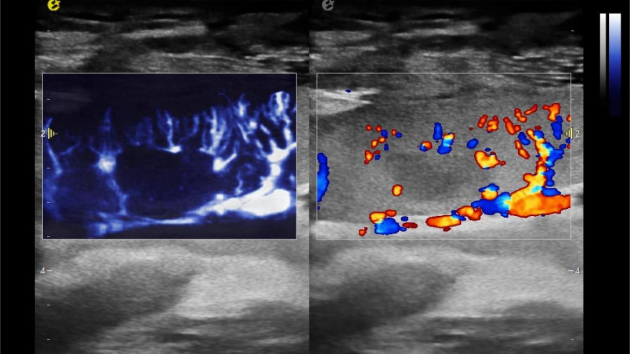

2) 可检测20-50μm级细小血管低速血流信号,能看清头发丝1/2粗细的微血管;

微米级超高分辨率血流信号显像

超微视血流显像评估肾移植术后灌注情况

这一项无创、无辐射操作简便且无需造影剂的黑科技,相当于用"高速摄像机"记录血液细胞的运动轨迹,让血管并发症"无处遁形。

从术前评估到术中到术后,再到终身监护,当20-50μm级的超微血流信号在屏幕上跳动,我们看到的不仅是技术的精进,更是生命的律动。iPlane Vascular正在重新定义肾移植监护的标准——让医生拥有了"显微视力",让每一个微小血管的异常都无所遁形,让每一次免疫排斥的萌芽都被及时扼制。